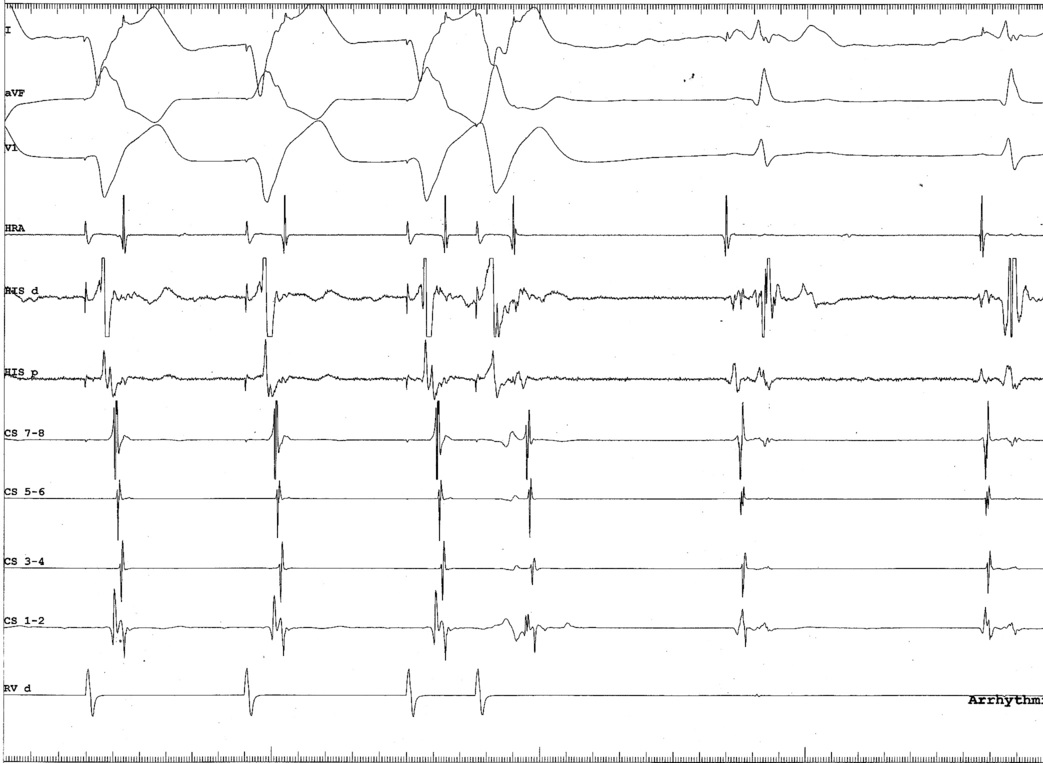

AP slant - Earliest A and earliest V may be distant

ap_med_lat.jpg

AP slant - AP potential more important

pot_late_a.jpg